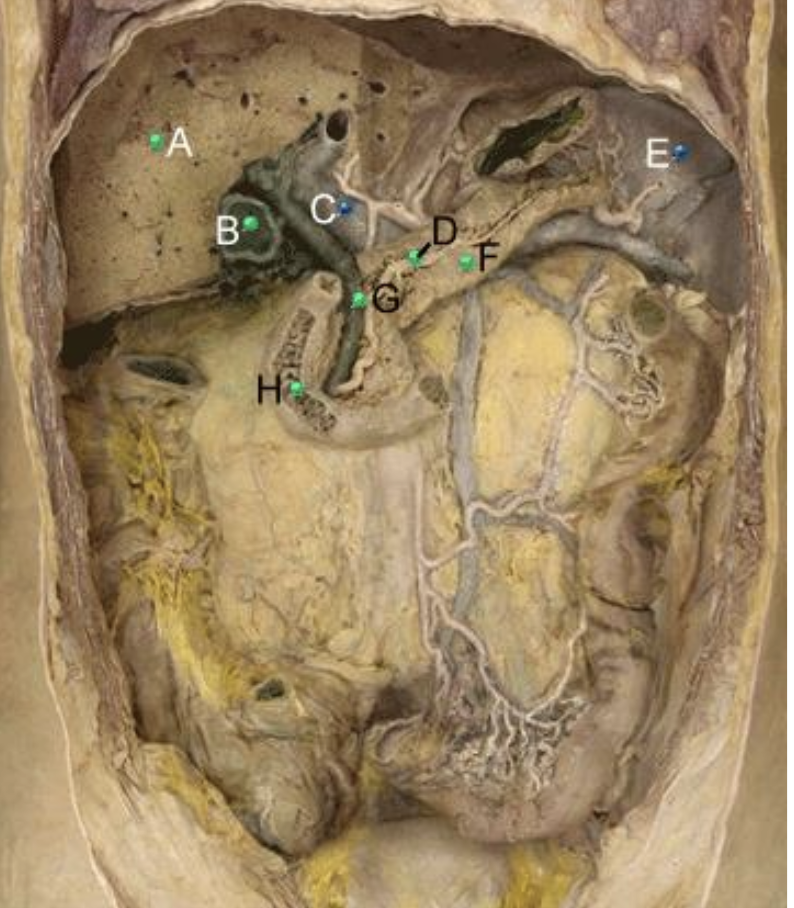

Part A?

Liver

Part B?

gallbladder

Part C?

hepatic portal vein

Part D?

Pancreatic duct

Part E?

spleen

Part F?

Pancreas

Part G?

bile duct

Part H?

duodenum